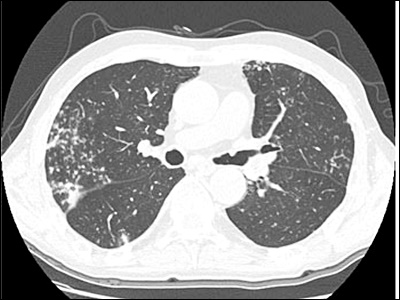

결핵의 주요 증상들 상세 분석

결핵은 폐결핵, 림프절 결핵, 뼈 결핵 등 다양한 형태로 나타날 수 있습니다. 각각의 증상을 상세히 분석하여 이해할 수 있습니다.